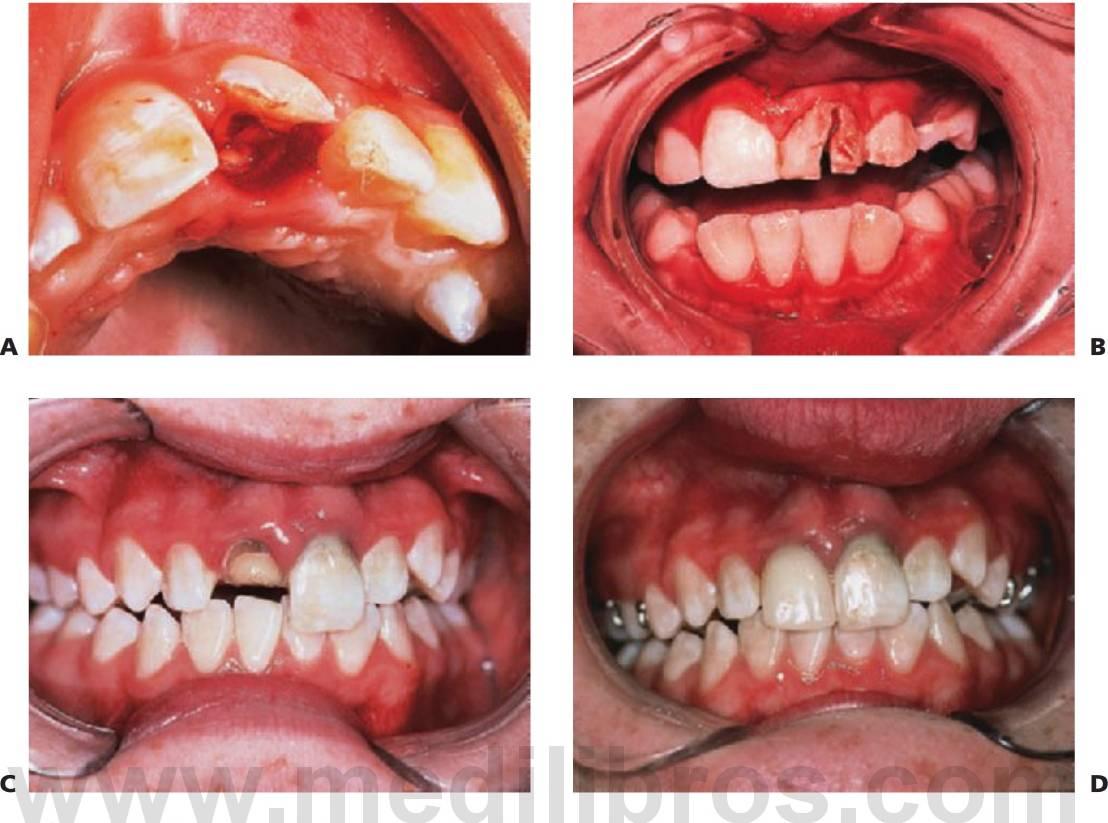

El tratamiento de los traumatismos dentoalveolares, que suele resultar angustioso para los niños y para los padres (fig. 7.1), con frecuencia resulta también difícil para el especialista, si bien se encuentra entre las causas más habituales de visita del niño al odontopediatra. La urgencia del paciente debe constituir una rutina para el especialista y siempre debe elaborar se un exhaustivo examen del niño antes de comunicar a los padres las eventuales necesidades de tratamiento, pues muchos casos podrían carecer de la gravedad que parecía en un principio. Ante todo, se debe tranquilizar tanto a los padres como al niño, pues un traumatismo no sólo compromete una dentición sana, sino que puede también ocasionar un defecto que afecte a la autoestima y a la calidad de vida del paciente y le obligue a un mantenimiento odontológico de por vida.

La región orofacial sufre la mayor afectación de traumatismos durante los episodios de maltrato infantil (fig. 7.2) y estos traumatismos no accidentales tienen como resultado diferentes tipos de lesiones, como las lesiones que no concuerdan con el relato ofrecido, los hematomas en tejido blando que no cubren prominencias óseas, las lesiones que adquieren la forma de un objeto reconocible o la multitud de lesiones que aparecen en el mismo niño a diferentes edades; asimismo, las marcas de mordeduras en niños se consideran maltrato infantil hasta que se prue be lo contrario. Para establecer la adecuada notificación, tratamiento y prevención de más lesiones, deben ser del total conocimiento del especialista tanto las características y las conclusiones del diagnóstico de maltrato infantil como el protocolo para denunciar tales hechos.

La exploración debe llevarse a cabo siguiendo un orden lógico. Resulta importante examinar todo el cuerpo, pues el paciente podría presentarse en primer lugar en la consulta del especialista dental pero haber sufrido otro tipo de lesiones (fig. 7.3 y v. cap. 1).

Las fracturas de los huesos faciales no son habituales en niños y representan menos del 5% del total de las fracturas maxilofaciales. En consecuencia, pocos cirujanos presentan una vasta experiencia en esta área, si bien el enfoque que hagan de estos casos deberá valorar las implicaciones de dichas lesiones en el crecimiento del niño (fig. 7.7).